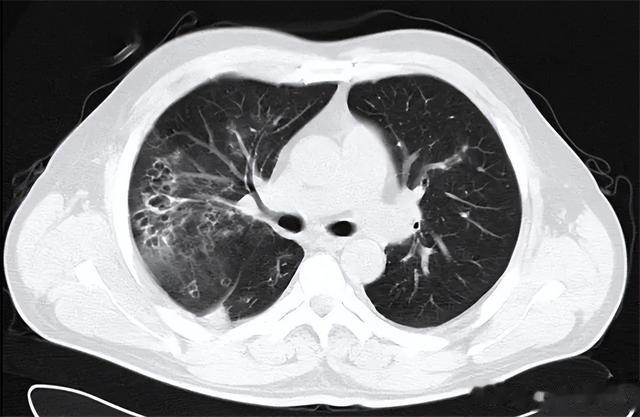

查体发现李大叔双肺下端可听及明显的湿性啰音 , 随后经X线检查显示李大叔双肺下端的肺纹理呈条索状、明显增粗 , 验血发现血液中的白细胞和中性粒细胞计数高于正常值 , 且痰液培养中含有革兰氏阳性菌和大量被破坏的淋巴细胞 。